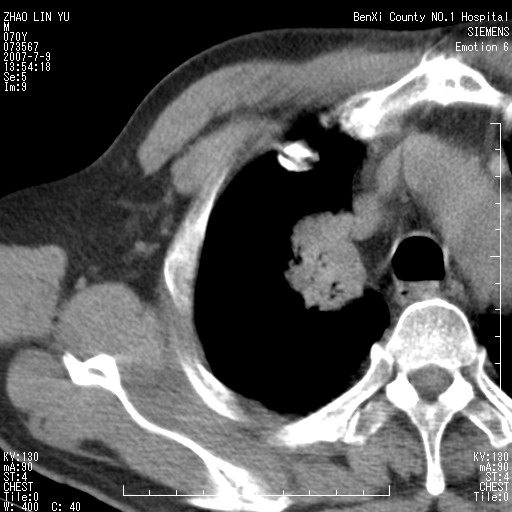

以下是引用王靖旗在2007-7-10 17:12:00的发言:[br] 男、70、咳嗽两个月,半年前换瓣手术,胸片未见异常,于昨天行x片发现右肺上野大片影,行ct扫描,这里是减薄图像,余肺正常。明天晚上会有增强扫描片,到时我会上传。[br][br] 冠状位请大家细看,应该是有意义的,[br][br] 请大家先看平扫发表意见。[br][br]

以下是引用zhangzhongshou在2007-7-10 21:43:00的发言:[br]右肺上叶周围型肺癌,以孤立型细支气管肺泡癌可能性大。